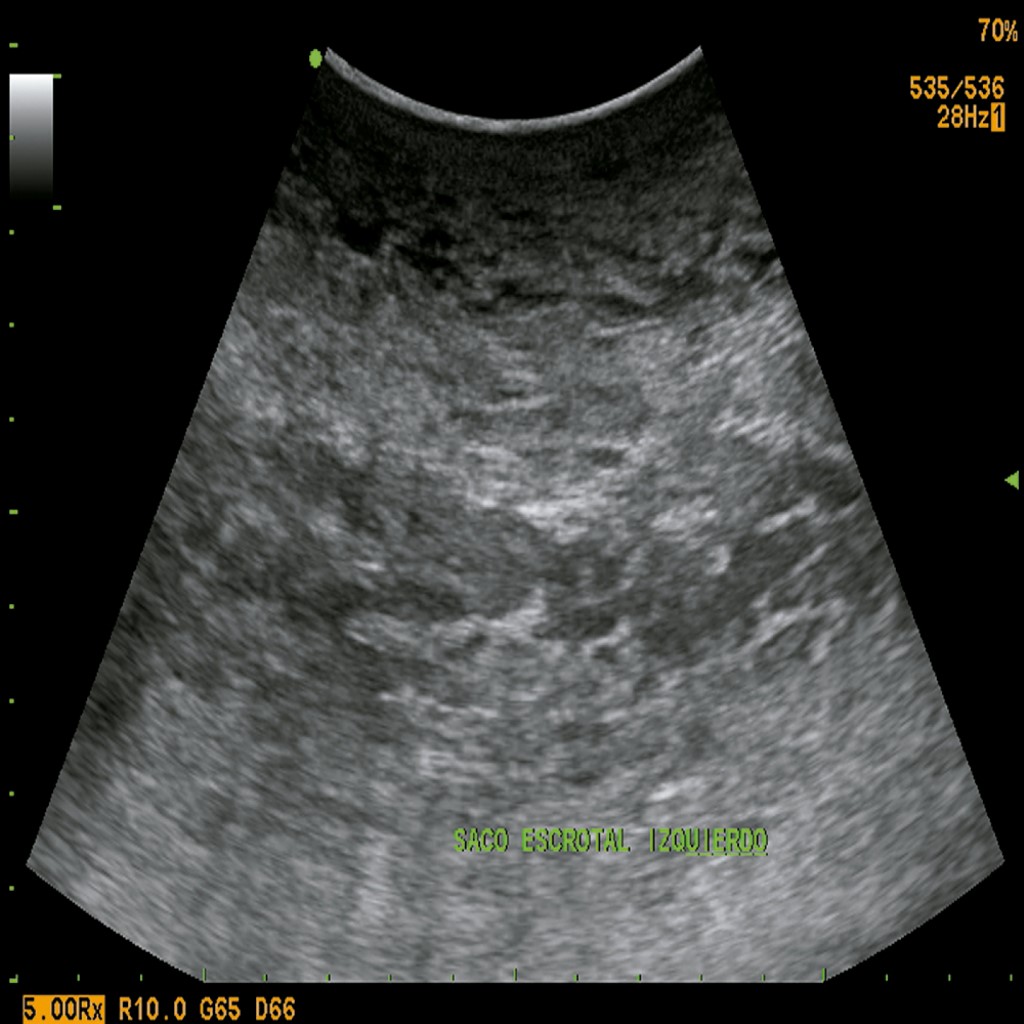

Paciente masculino de 32 años de edad, mexicano, de origen étnico mestizo, ocupación taxista, con antecedentes personales de sedentarismo, obesidad mórbida (índice de masa corporal [IMC] = 57), quien acude a consulta por presentar una hernia inguinoescrotal izquierda de 10 años de evolución. Al examen físico se confirma que el paciente presenta una hernia inguinoescrotal que excede el borde superior de la patela izquierda y cambios tróficos de la piel escrotal (Figura 1). El ultrasonido inguinal mostró un saco herniario de contenido intestinal y omental. Durante su estancia hospitalaria se inicia con NPP mediante la introducción de una aguja de Veress en el punto de Palmer. Se insuflaron 200 cm3 de aire ambiente con jeringa de 100 cm3. Posteriormente, se colocó catéter de doble luz (subclavio) con la técnica de Seldinger. Se insuflaron 800 cm3 de aire ambiente y se corroboró la presencia de neumoperitoneo mediante una radiografía de tórax en bipedestación. Se administraron 1,000 cm3 cada 24 horas durante 21 días hasta un volumen total de 21,000 cm3.

Figura 1

Figura 5